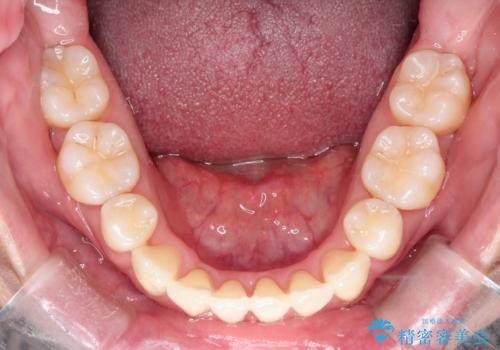

【抜歯ケース】前歯のガタガタをインビザラインで治療

- 前歯のガタガタを主訴に来院されました。

抜歯が必要なケースでしたが、インビザラインでの治療を希望されワイヤーを使用せずに治療を完了しております。